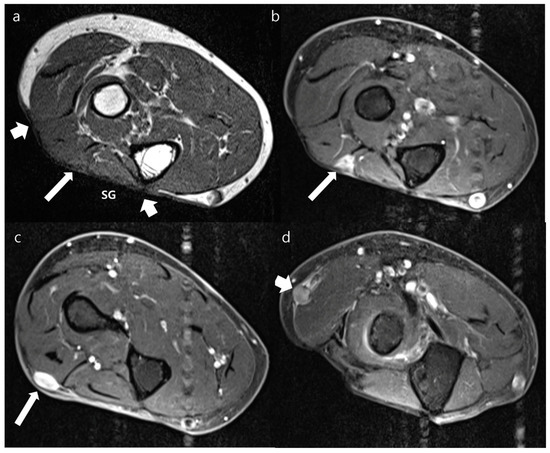

3.2. Morphology of Recurrent Tumors

3.3. MRI Signal Intensity of Recurrent Tumor

3.4. Diagnostic Performance of MRI Features for Diagnosing Local Recurrence